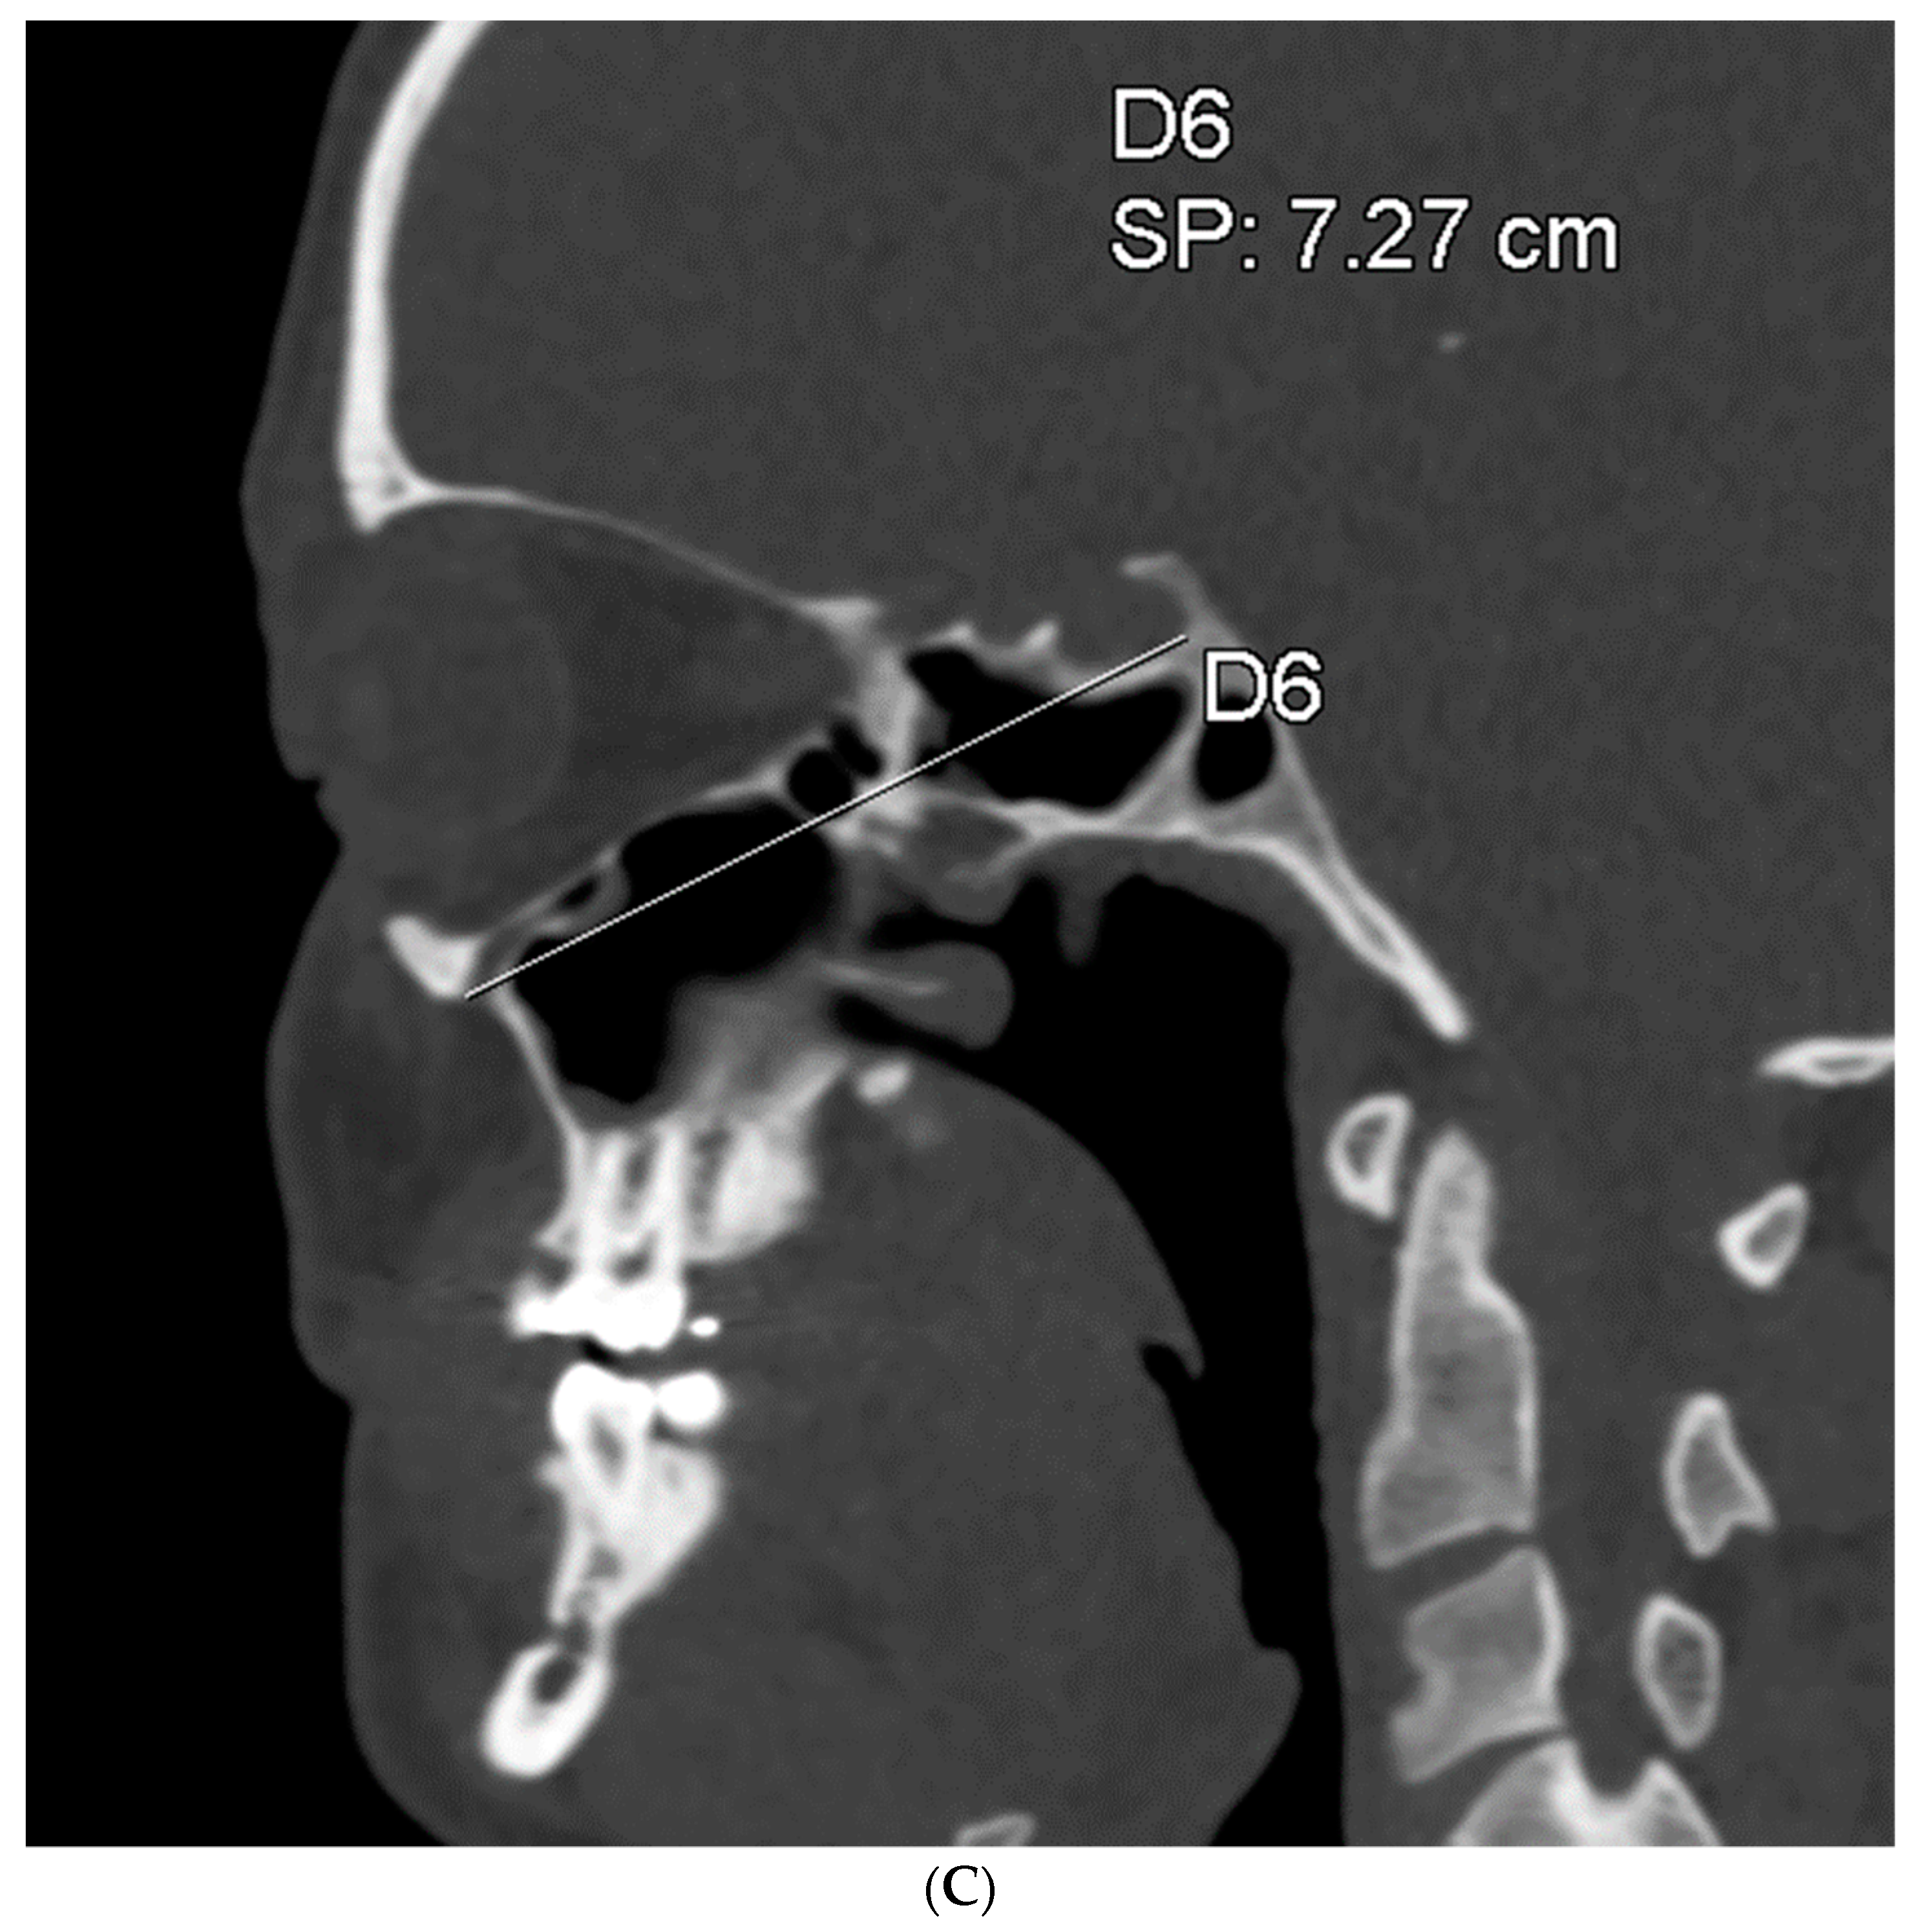

To assess the size of the rim of bony orbit, the width and height were measured from the most anterior CBCT or CT slice showing the whole orbital rim (Figure 2A), and the depth was the distance from the frontozygomatic suture to the optic canal (Figure 2B). The position of bony orbit was assessed as the distance of the cranio-lateral border of the infraorbital canal opening to the inner postero-caudal wall of the sella turcica, measured from an oblique sagittal plane (Figure 2C). Helsinki University Hospital radiologist workstations and Syngo software (Siemens Healthineers, Erlangen Germany) were used for the analysis according to the manufacturer’s instructions for quantitative analysis. The volume of bony orbit was measured with semi-automated segmentation to avoid potential measurement-related bias since the cleft side is always visible to the radiologist in the lower sections during the orbital analysis. Semi-automated orbital volume analysis was performed using CMF Orbital Software (Disior Ltd., Helsinki, Finland). To use the software, the radiologist only selects a seed point inside the orbital vault and confirms the side to be examined. The apex of the orbit at the conjunction of the optic nerve and bulbus was used as a seed point in all cases. After selecting the seed point, the virtual program-generated triangle mesh iteratively expands from the starting position until it meets the bony walls of the orbit. The anterior expansion of the volume mesh network automatically stops when the mesh reaches the bony rim of the orbit (Figure 3). This system is described in more detail, and the reliability of the software measurements is proven to be high (0.992 (95% CI 0.987–0.997 intraobserver ICC and 0.989 (95% CI 0.983–0.993)) interobserver ICC in intact orbit) [25]. All volume analyses and the surface reliability of the software algorithm were confirmed by the radiologist in all cases. All the measures of the cleft patients were made by the same radiologist (E.P.).

Figure 2.

(A) The width and height of the bony orbit from the most anterior CBCT or CT slice showing the whole orbital rim. (B) The depth from the frontozygomatic suture to the optic canal opening. (C) The position of bony orbit was assessed as the distance of the cranio-lateral border of the infraorbital canal opening to the inner posterocaudal wall of sella turcica, measured from an oblique sagittal plane.